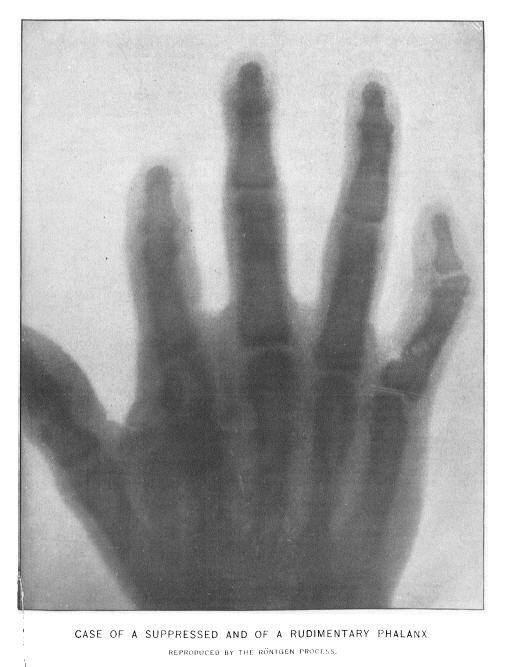

1895年12月1日

德国物理学家Wilhelm Roentgen(伦琴)发线了x射线。在发现x射线后的两周左右,伦琴给他的妻子的手拍了张照片,当她的妻子看到了自己的骨骼,惊呼"我看到了自己的死亡"。